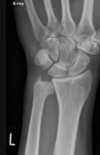

Fratura de Chaffeur

Fratura do processo estilóide do rádio.